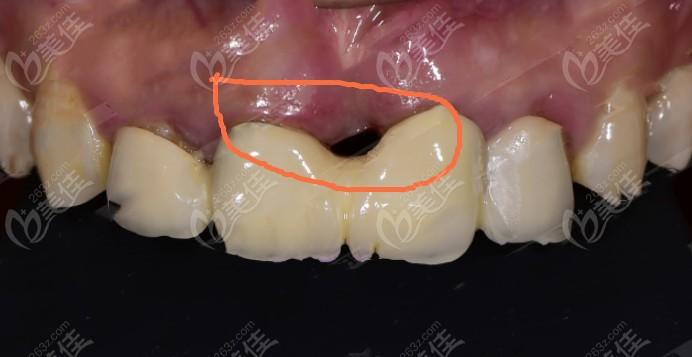

帮忙看看刚种的三颗是否歪了,感谢!_种植牙_医疗健康

种植牙牙体种歪了图片